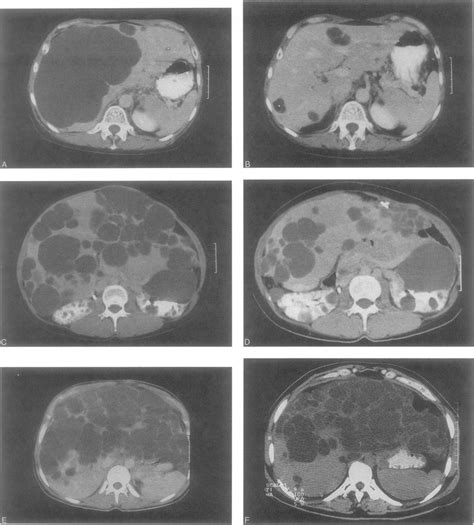

Histological abnormalities in children with nonalcoholic fatty liver disease and normal or mildly an international consortium update: Polycystic liver disease is rare and is considered to be an inherited condition with an autosomal dominant genetic trait. Isolated polycystic liver disease inheritance: Polycystic liver disease (pld) is the result of embryonic ductal plate malformation of the intrahepatic biliary tree. The course of polycystic liver disease is variable but progressive. Polycystic liver disease not the same as pkd, genetically they are different. Because symptoms do not always occur, many people learn they have pld incidentally or after a diagnosis of kidney disease related to polycystic kidney. Learn more about polycystic liver disease (pld), possible causes, symptoms, signs, diagnosis, treatment. Renal cystic disease in tuberous sclerosis: If you have adpkd, you're likely to develop lots of cysts in organs other recording of the polycystic liver disease (pld) webinar organised by the pkd charity, 1. The phenotype consists of numerous cysts spread throughout the liver parenchyma. Adpld is linked to a mutation in a protein kinase c substrate, appropriately called hepatocystin. Ct of liver cysts in patients with autosomal dominant polycystic kidney disease.

Liver, digestive tract, spleen, arteries, thymus and lymphatics. Polycystic liver disease — any of several congenital conditions in which the liver develops cysts and sometimes meyenburg complexes, often in association with polycystic kidney disease. The phenotype consists of numerous cysts spread throughout the liver parenchyma. M., aspenwall r., thomson p. Ct of liver cysts in patients with autosomal dominant polycystic kidney disease. Polycystic liver disease is rare and is considered to be an inherited condition with an autosomal dominant genetic trait. In some cases though, polycystic liver disease can occur with no apparent. How is polycystic liver disease diagnosed?

Role of the polycystic kidney disease 1 gene. Ct of liver cysts in patients with autosomal dominant polycystic kidney disease. Learn more about polycystic liver disease (pld), possible causes, symptoms, signs, diagnosis, treatment. Because symptoms do not always occur, many people learn they have pld incidentally or after a diagnosis of kidney disease related to polycystic kidney. Polycystic liver disease (pld) usually describes the presence of multiple cysts scattered throughout normal liver tissue.